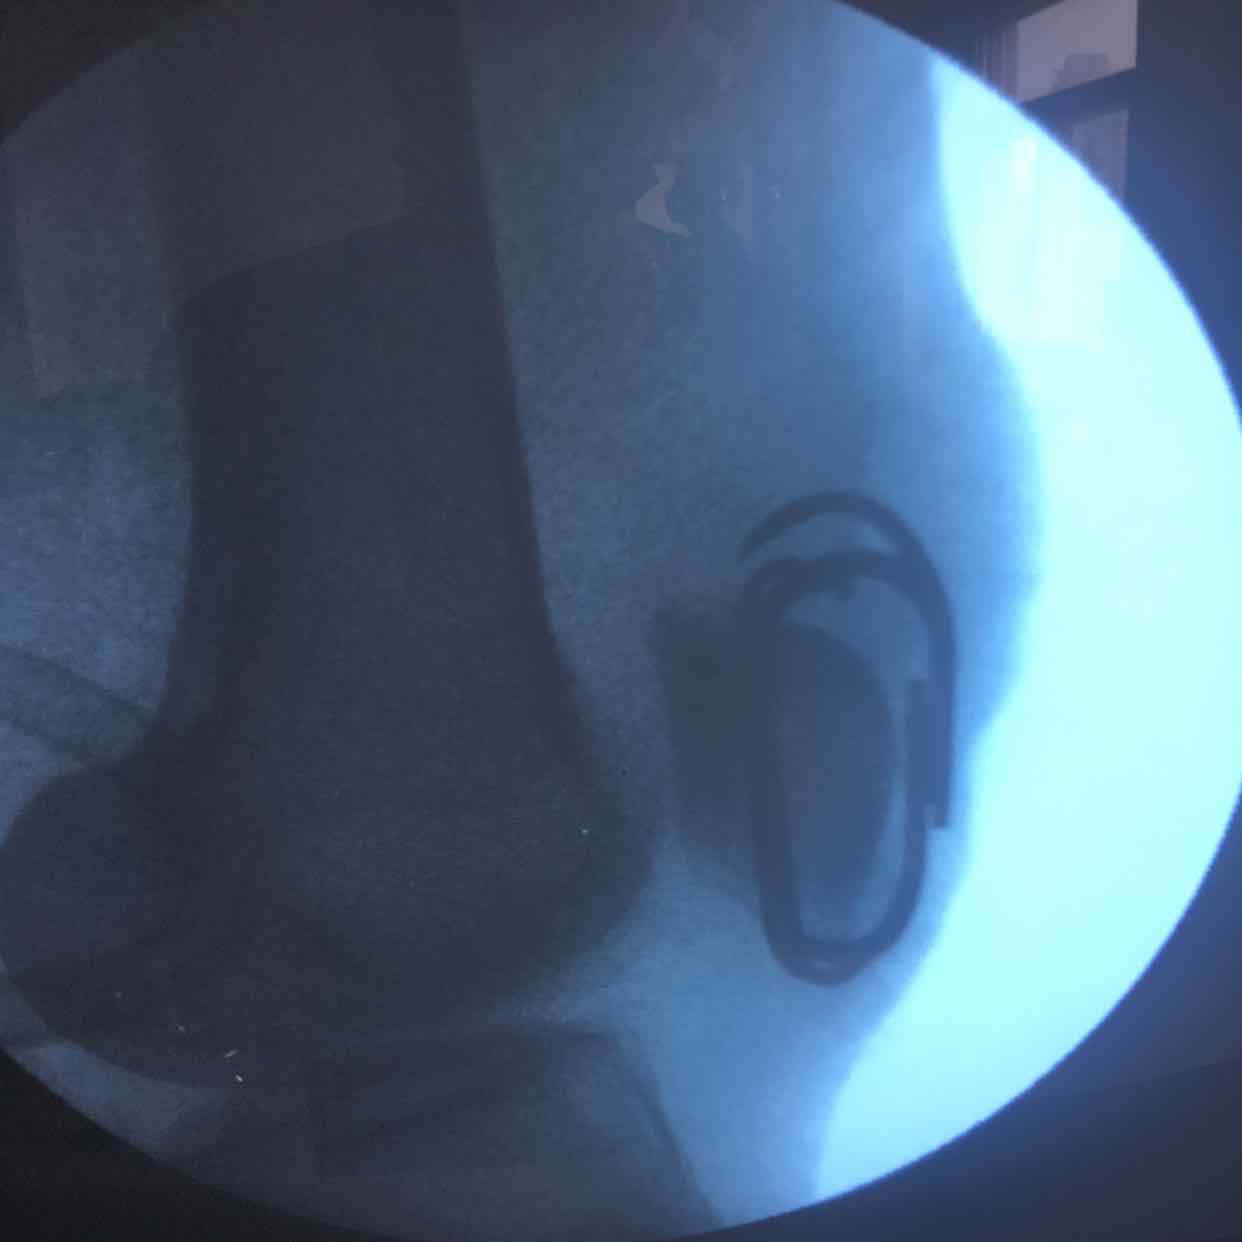

髌骨骨折(髌骨爪➕克氏针固定)

骨折 髌骨骨折

生命体征平稳,心肺复未见异常。左膝部肿胀明显,局部皮色皮温正常,压痛明显,可及骨檫音,骨檫感,伸膝关节受限,末梢血运感觉正常。

诊断左髌骨骨折在腰麻下行切复内固定术,术后抗炎,消肿等处理。